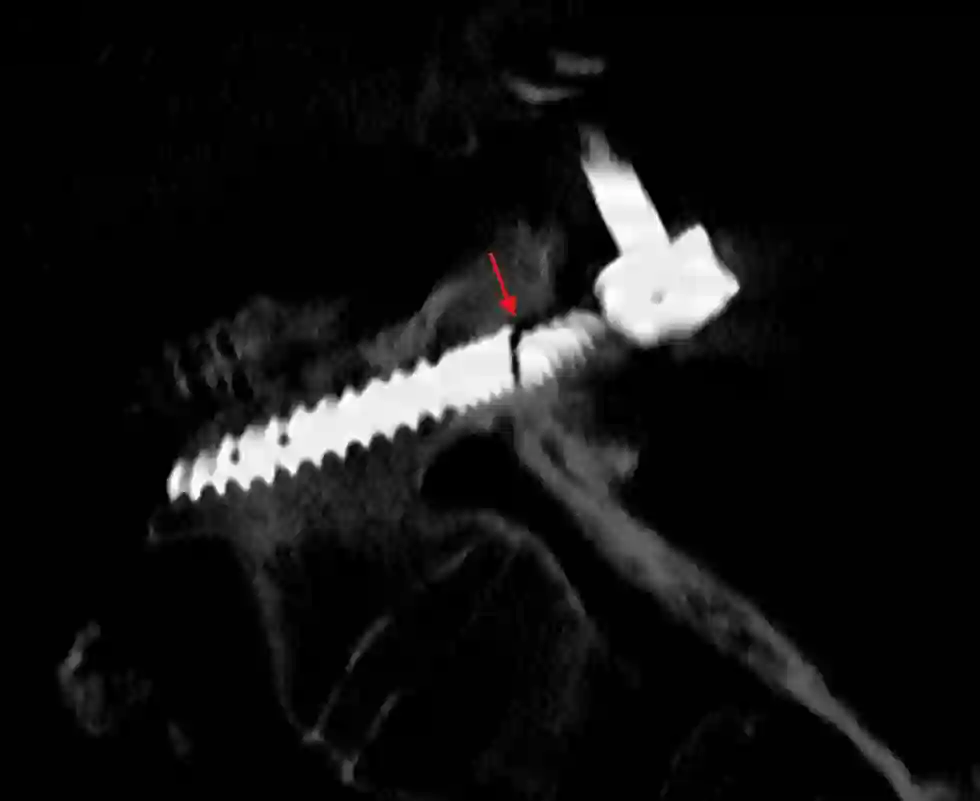

Seit einigen Jahren sind Karbonpedikelschrauben verfügbar. Pedikelschrauben aus Karbon haben den Vorteil, dass diese weniger Artefakte in der MRT Bildgebung verursachen[^3]. Dies ist insbesondere für Patienten mit Tumorleiden an der Wirbelsäule von Vorteil, um eine optimale Nachbehandlung zu planen.